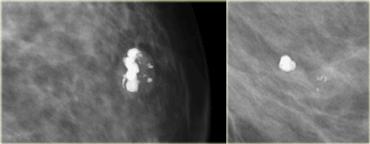

TRÁI: cụm vôi hóa đa hình thái trên tư thế chếch | PHẢI: sữa canxi (hình tách trà) trên tư thế bên với chùm tia nằm ngang